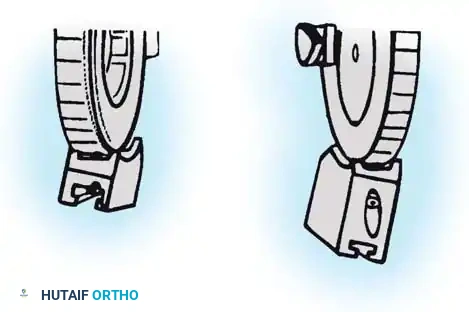

Fig. 58-27 Design features of the hinged elbow external fixator, noting the built-in 7 degrees of valgus to approximate the distal humerus anatomy.

Preoperative assembly is vital. The hinge block must be configured so the large block sits medially. The differential block height accommodates the average 7 degrees of distal humeral valgus, ensuring the upper ring remains perpendicular to the humerus while the axis of rotation is perfectly aligned.

The Compass hinge arrives assembled for a right arm.

Fig. 58-28A The Compass hinge in its default right arm configuration.